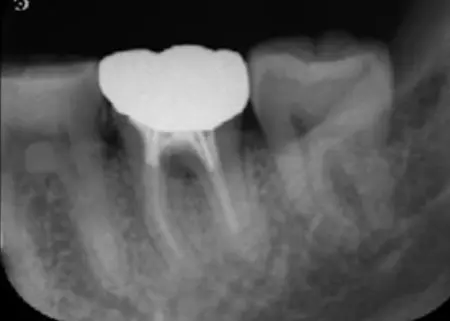

治療前

治療後

レントゲン撮影を行って詳しく拝見したところ、左下奥歯の歯根の先に膿があることがわかりました。

この歯には過去に、細菌感染した神経を取り除き、神経が入っていた細い管を清掃して薬を詰める「根管治療」が施されています。しかし再度細菌に感染し、歯根の先に炎症が起きて膿が溜まる「根尖性(こんせんせい)歯周炎」を発症している状態です。

CTを撮影してさらに詳しく検査を行った結果、以前の根管治療後には神経の代わりに薬を詰める処置「根管充填」が適切に行われていることが確認できましたが、現在は炎症が広がり、歯根の周囲にある骨も溶けています。

今回は、歯根の内部を徹底的に洗浄・消毒して細菌を除去するために、歯科用顕微鏡「マイクロスコープ」を使用した「精密根管治療」を行います。

まずは、マイクロスコープを使って歯根の内部を丁寧に清掃し、感染した組織を取り除きます。その後、根管内を殺菌し、再び細菌に感染しないようしっかりと密閉しました。また、この歯には3本の根管があるため、それぞれ慎重に治療しています。

3回目の受診時には、CTの撮影をして以前歯根の先に見られた炎症や膿の有無を確認しましたが、問題がなかったため、歯の型取りをしてゴールドクラウンの作製を開始しました。

最後の受診時には、完成したゴールドクラウンを装着し、噛み合わせに問題がないことを確認して、治療を終了しています。